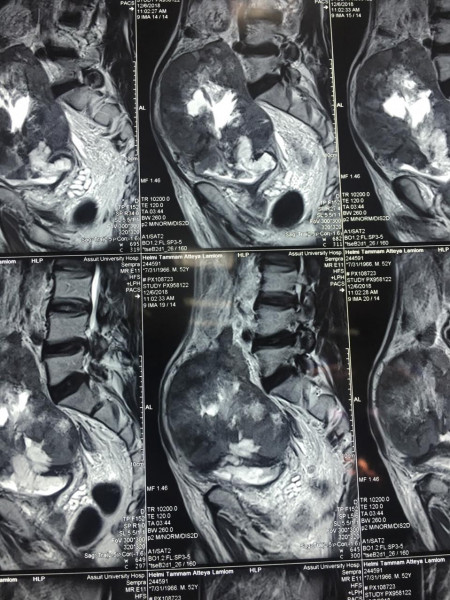

كما كشف الدكتور عمرو أبو فدان المدرس بقسم جراحة المسالك وعضو الفريق الطبي المسئول عن العملية انه فور وصول المريض إلى المستشفى تم خضوعه لعدد من الإشاعات والفحوصات الأولية والتي بينت تضخم حجم الورم مما يستلزم التدخل الجراحي لفصل الورم عن الأنسجة المحيطة وإنقاذ حياه المريض وبالفعل تم إجراء الجراحة بنجاح وخرج المريض من غرفة العمليات دون أي مضاعفات كما تم متابعة الحالة فى غرفة العناية المركزة لمدة 24 ساعة وعند استقرار حالة المريض تم نقله إلى غرفته بمستشفى جراحة المسالك البولية والكلى.